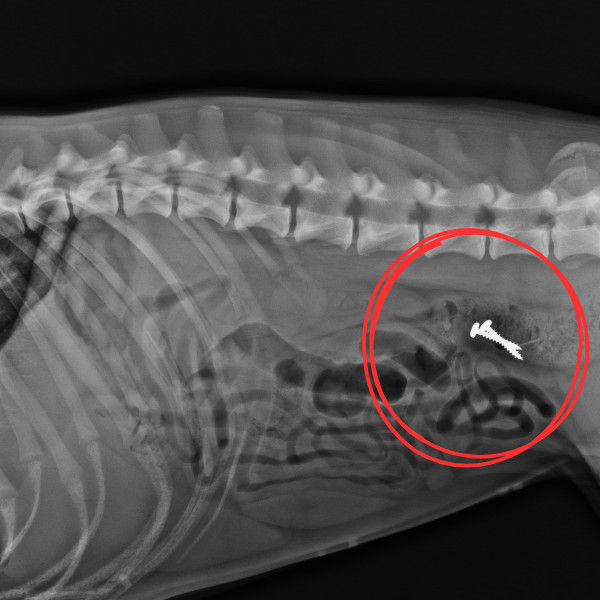

能清楚的看到,流浪狗在吃著麵包,但那些麵包其實被惡意加工、藏著「鐵釘」,甚至還有「鐵釘熱狗」及「鐵釘培根肉丸」或「毒罐罐」;「這世界上仍有許多惡人以捉弄飢餓的流浪動物為樂」,並呼籲,「請大家不要虐待動物」。

浪浪時常處於飢餓狀態、根本飢不擇食,這些藏有毒物的食物不僅會對牠們造成嚴重傷害、甚至還可能造成牠們死亡,因此,這種惡劣又殘忍的虐狗行徑遭到撻伐!「實在太殘忍」、「看了心很痛」。